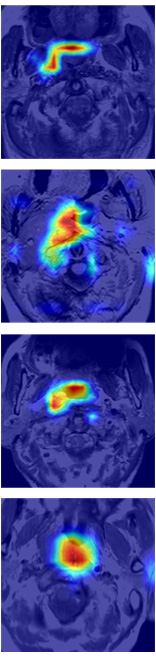

Some examples of spatial attention coefficients are shown in Figure 11. We can see that, several locations may fire at the beginning of training phase and then energy will slowly build up over ROIs and reduce the attention to false positives.